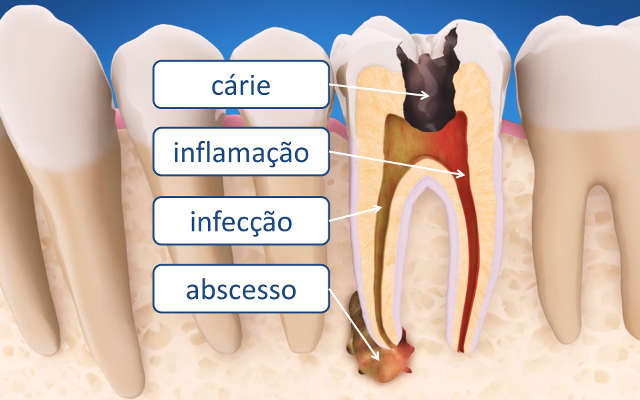

A Descoberta da Causa Raiz: Tudo começa com uma investigação minuciosa. O dentista usa radiografias para identificar a extensão do problema, como cáries profundas, fraturas ou traumas que levaram à inflamação ou infecção da polpa. É o primeiro passo para planejar a intervenção.

O Coração do Dente: A polpa dental é o tecido mole no interior do dente, que abriga nervos e vasos sanguíneos. Quando ela é afetada por cáries profundas, traumas ou infecções, o tratamento endodôntico se torna necessário para remover essa parte comprometida.

A Luta Contra as Bactérias: O interior do dente, após a remoção da polpa infectada, ainda pode abrigar microrganismos. A desinfecção visa eliminar essas bactérias, limpando a fundo os canais radiculares e os túbulos dentinários.